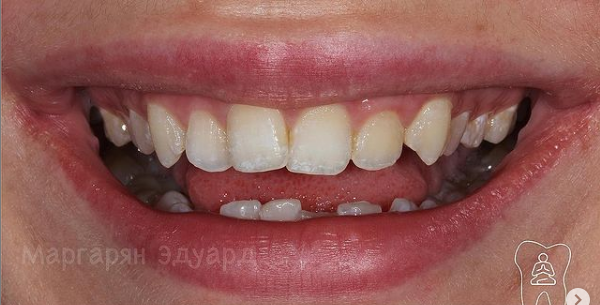

12 работ в портфолио

Маргарян Эдуард Вадимович принимает в МЕДИЦИНСКОМ СТОМАТОЛОГИЧЕСКОМ ЦЕНТРЕ НА ЗЕЛЕНОГРАДСКОЙ в Москве. Стаж 13 лет. Специализируется на ортопедии. Имеет 12 работ до/после в портфолио. Для уточнения дополнительной информации о специалисте или записи на прием можно позвонить по телефону

Установка керамических виниров

Установка виниров E-max

Протезирование зубов

Установка коронки на зуб